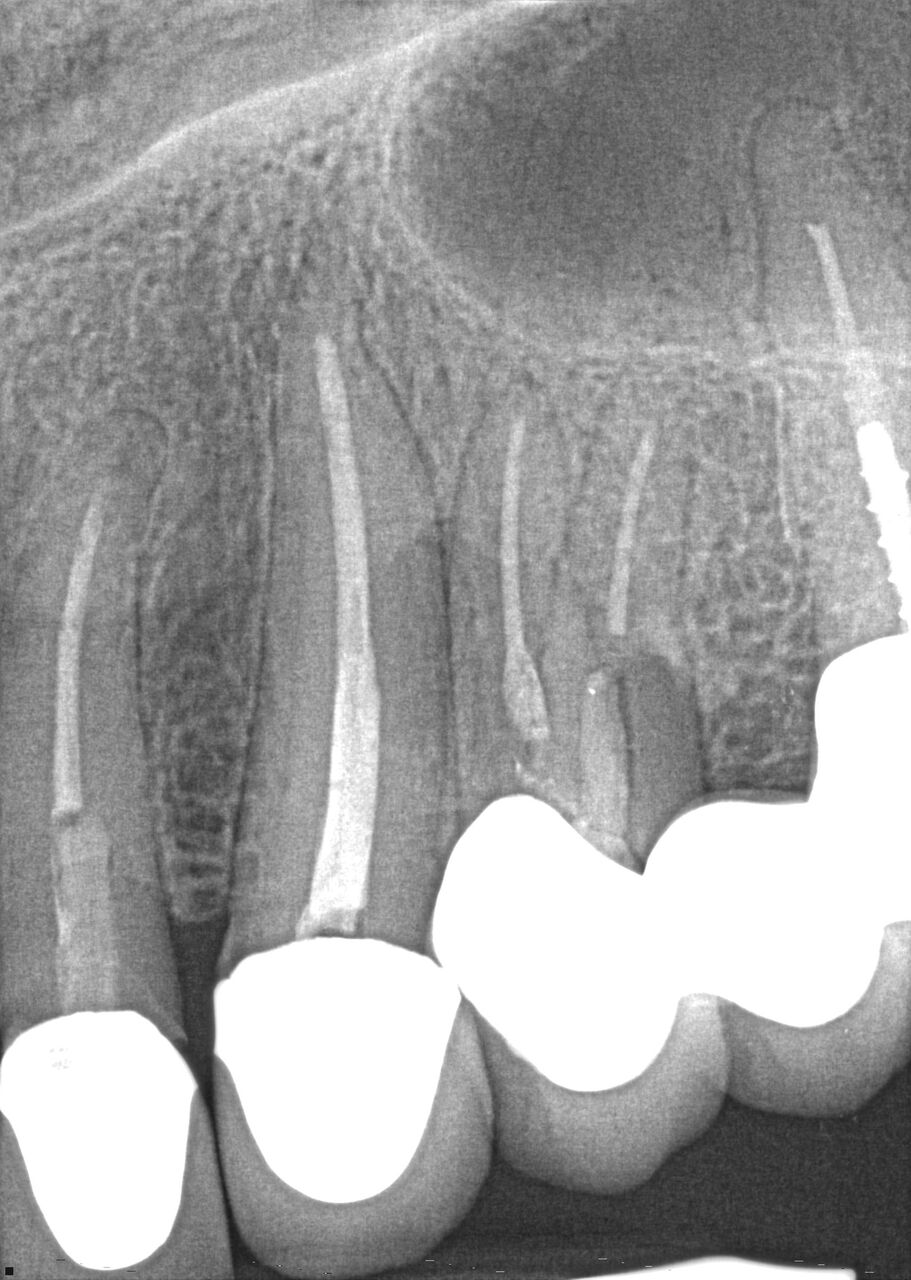

(8.) Case 2 initial radiograph of Nos. 12 through 14 with disunion of No. 12 crown to underlying root.

Figure 8

( 9.) Case 2 initial radiograph of Nos. 12 through 14 with disunion of No. 12 crown to underlying root.

Figure 9

A 67-year-old woman presented on an emergency basis with a bad odor and taste from crown No. 12, which had been diagnosed that day at hygiene recall as decayed and no longer attached to the underlying root (Figure 8 and Figure 9). The patient was anesthetized and the existing bridge was sectioned (Figure 10), leaving crown No. 14 intact. The No. 12 root was extracted and the site was fully debrided of granuloma. A platform shift implant was stabilized in excess of 45 Ncm in position No. 12, which was prosthetically correct. The soft tissue of pontic site No. 13 was contoured to mimic soft tissue contours of a bicuspid and an implant was secured in excess of 45 Ncm. Implant No. 13 was milled to allow for unimpeded seating of the temporization abutment, whereas implant No. 12 did not need milling as it was a platform-shift implant. The existing crown No. 12 and cantilever No. 13 were revised to be a temporary bridge on Nos. 12 and 13 (Figure 11 and Figure 12). The revised temporary bridge was positioned in infraocclusion and cemented after the extrusion of excess cement extraorally (Figure 13). No bone graft or sutures were placed as the temporary crowns sealed the sockets.